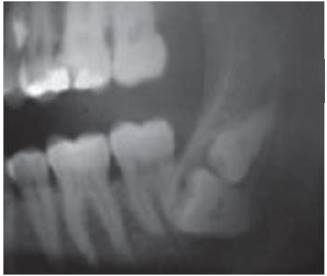

Fourth molars or distomolars, since they not always exhibit isolated symptomatology, are mostly found after X ray examinations conducted to treat third molar problems (Figure 24). Fourth molars are rarely found erupted, thus first findings are clinical.